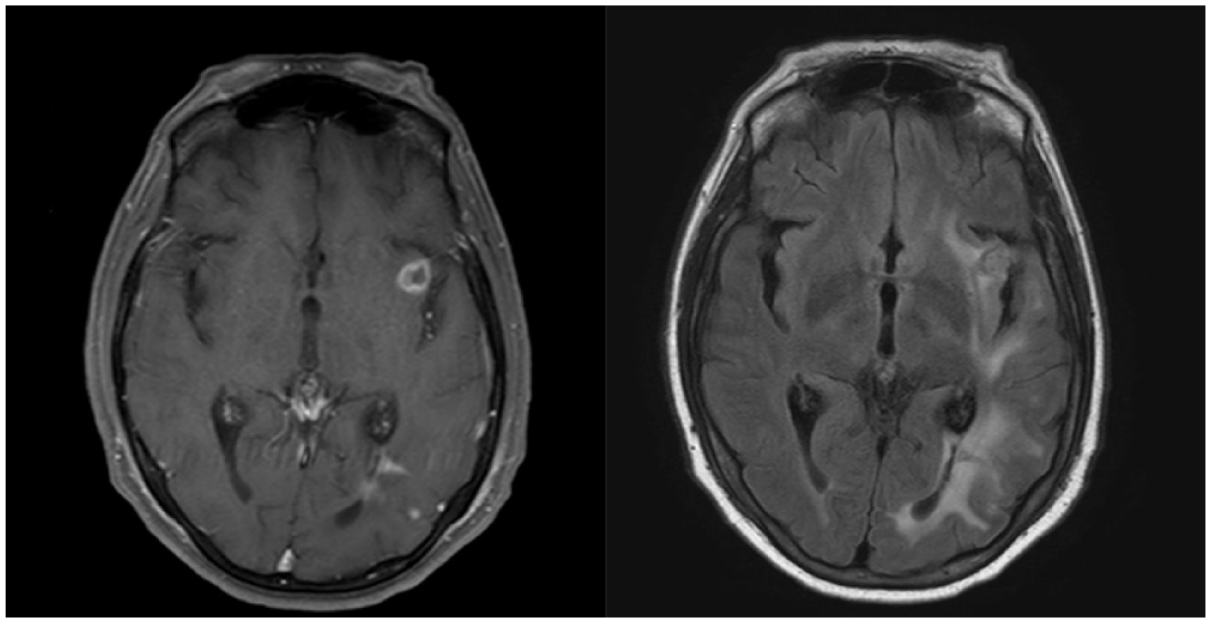

In imaging, multifocal lesions are more common than unifocal ones, primarily appearing in the lobar regions, followed by basal ganglia.20,108 Less typically, lesions can manifest in the periventricular areas, brainstem, cerebellum, or corpus callosum. 109 MRI lesions are typically reported as highly cellular tumors, which, due to their high risk of hemorrhage, often present with cystic and necrotic changes with surrounding edema. T1-weighted imaging predominantly demonstrates iso- or hypointense lesions, with a few reported cases having hyperintense or heterogeneous T1 signals. Given the mixture of solid areas with cystic and necrotic changes, the T2-weighted (T2W) imaging varies in appearance and might present with hypo-, iso-, or hyperintense lesions. T2W images reflect the surrounding edema, which ranges from mild to extensive depending on the size of the lesions.3,20 See Figure 3 as an example of MRI lesions in a patient with CNS-PTLD.

Imaging findings of PTLD on MRI. Axial brain images of a patient presenting with CNS-PTLD. (a) T1-weighted post-gadolinium image shows a focal ring enhancing lesion in the left sub-insular region. (b) T2 weighted image (T2/FLAIR) with perilesional edema compromising the left hemisphere.